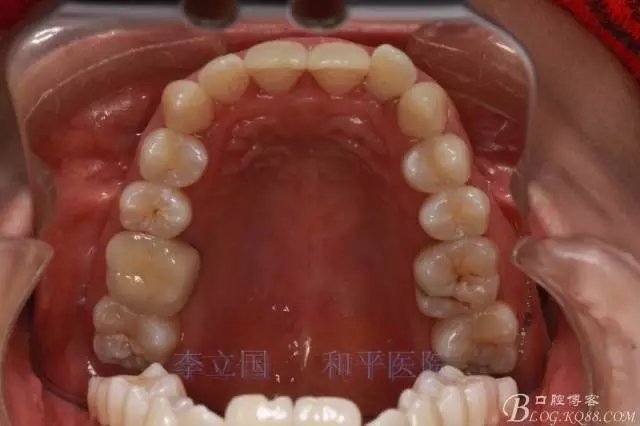

2.Damonclear排齊整平。

3.微種植支抗內(nèi)收上下前牙。

3.上頜應(yīng)用支抗釘。表麻下在56牙槽間隔植入,注意因使用的為鈦合金釘,一直保持植入角度與骨面成60度角,不要垂直植入再改變角度。要求即刻加載,即刻加載力值2盎司。

4.使用長牽引鉤,使?fàn)恳咏项M骨阻抗中心,防止上頜骨的順時(shí)針旋轉(zhuǎn)。